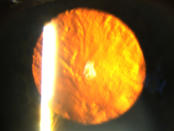

Klare Linse ohne Linsentrübungen

Eine Katarakt (links) verursacht ein unscharfes Bild durch vermehrte Lichtstreuung. Ein Linsen - tausch (rechts) korrigiert den Abbildungsfehler.

Eine Katarakt (links) verursacht ein unscharfes Bild durch vermehrte Lichtstreuung. Ein Linsentausch (rechts)  korrigiert den Abbildungsfehler.